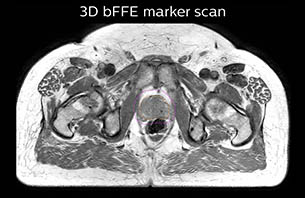

Using the mDIXON and 3D bFFE images, the RT planner marks the position of the nickel-titanium fiducial markers, and contours are transferred to the digitally reconstructed radiographs (DRRs). Reference image matching is based on these markers. “In the rare cases, where visualization of the fiducial markers fails, we do a CT to confirm their location,” Dr. Keyriläinen notes.

A 77-year-old male with prostate cancer cT3aN0M0, Gleason 8 and PSA 52 μg/L referred to androgen deprivation and radiation therapy with a prescribed dose of 50 Gy to the pelvic lymph node regions and 76 Gy to the prostate.

MR-only simulation workflow The 3D T1W FFE mDIXON sequence provides in-phase, water and fat images in one acquisition. Target and organs-at-risk are delineated on the 3D T2W TSE images. Prostate GTV is shown in orange, PTV in purple. The 3D bFFE sequence is used by the planner to mark the position of the fiducial markers (gold anchors) and contours are transferred to the digitally reconstructed radiographs (DRRs).